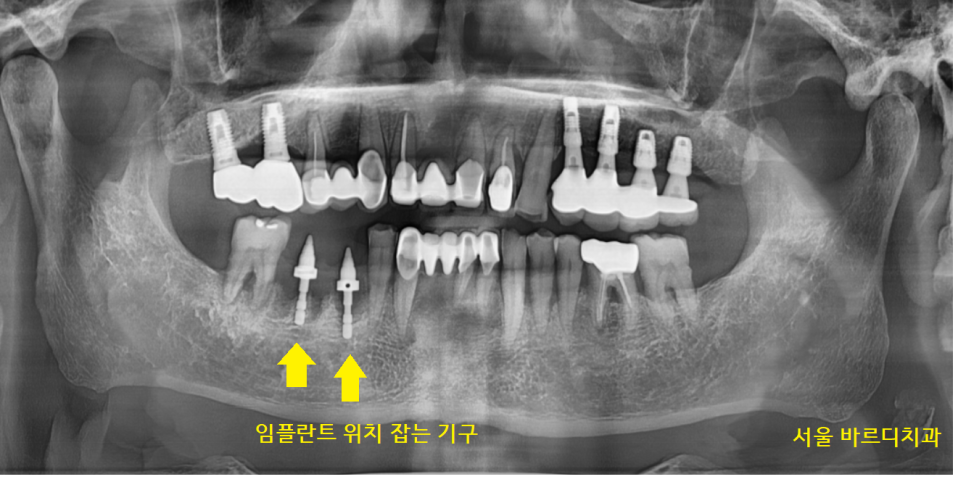

서울바르디치과는 수술 전 ct를 통해

-

예측 수술도 진행하지만..

정확한 수술을 위해 가이드 사용

- 수술 중 임플란트 위치 잡는 기구 사용

정확도를 높이기 위해 노력하는 병원입니다.

환자분이 편하게 쓰시려면

심을 때 제대로! 올바르게! 진행해야 하니까요.